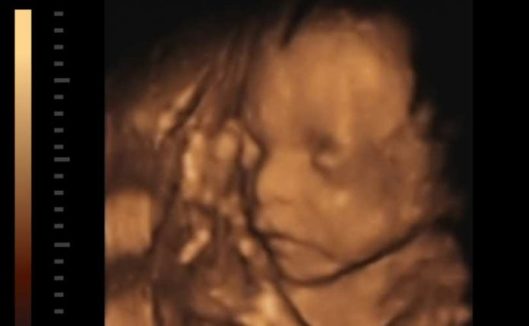

“Esta vez no es muy grande, 13 semanas” relató la mujer antes de la intervención. Sin hacer mucho caso de lo que decía, los trabajadores se pusieron a su tarea con cierta incomodidad por la reiteración de la protagonista. Y eso que practican abortos a diario.

El médico no vio inconveniente, y colocó los restos del feto en una bandeja. Los junto todos, como hacen siempre, para comprobar que no faltaba nada que se hubiese quedado dentro de Angie.